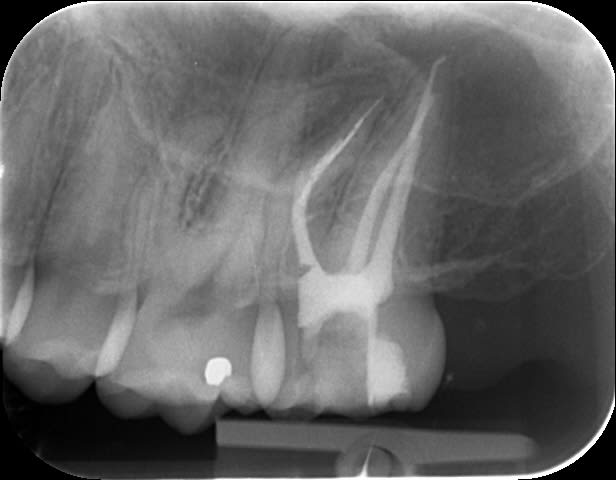

Une belle instrumentation en mésial, quelle tristesse.

Tout allait bien en progressant à patte de velours jusqu'à l'alésoir 30-4 trop fatigué apparemment (FKG Race), et j'ai donné un peu trop de force dans la progression verticale.

J'ai essayé de déloger la lime, j'ai cassé la deuxième puis la troisième.

Bon le canal est propre à défaut d'être étanche.